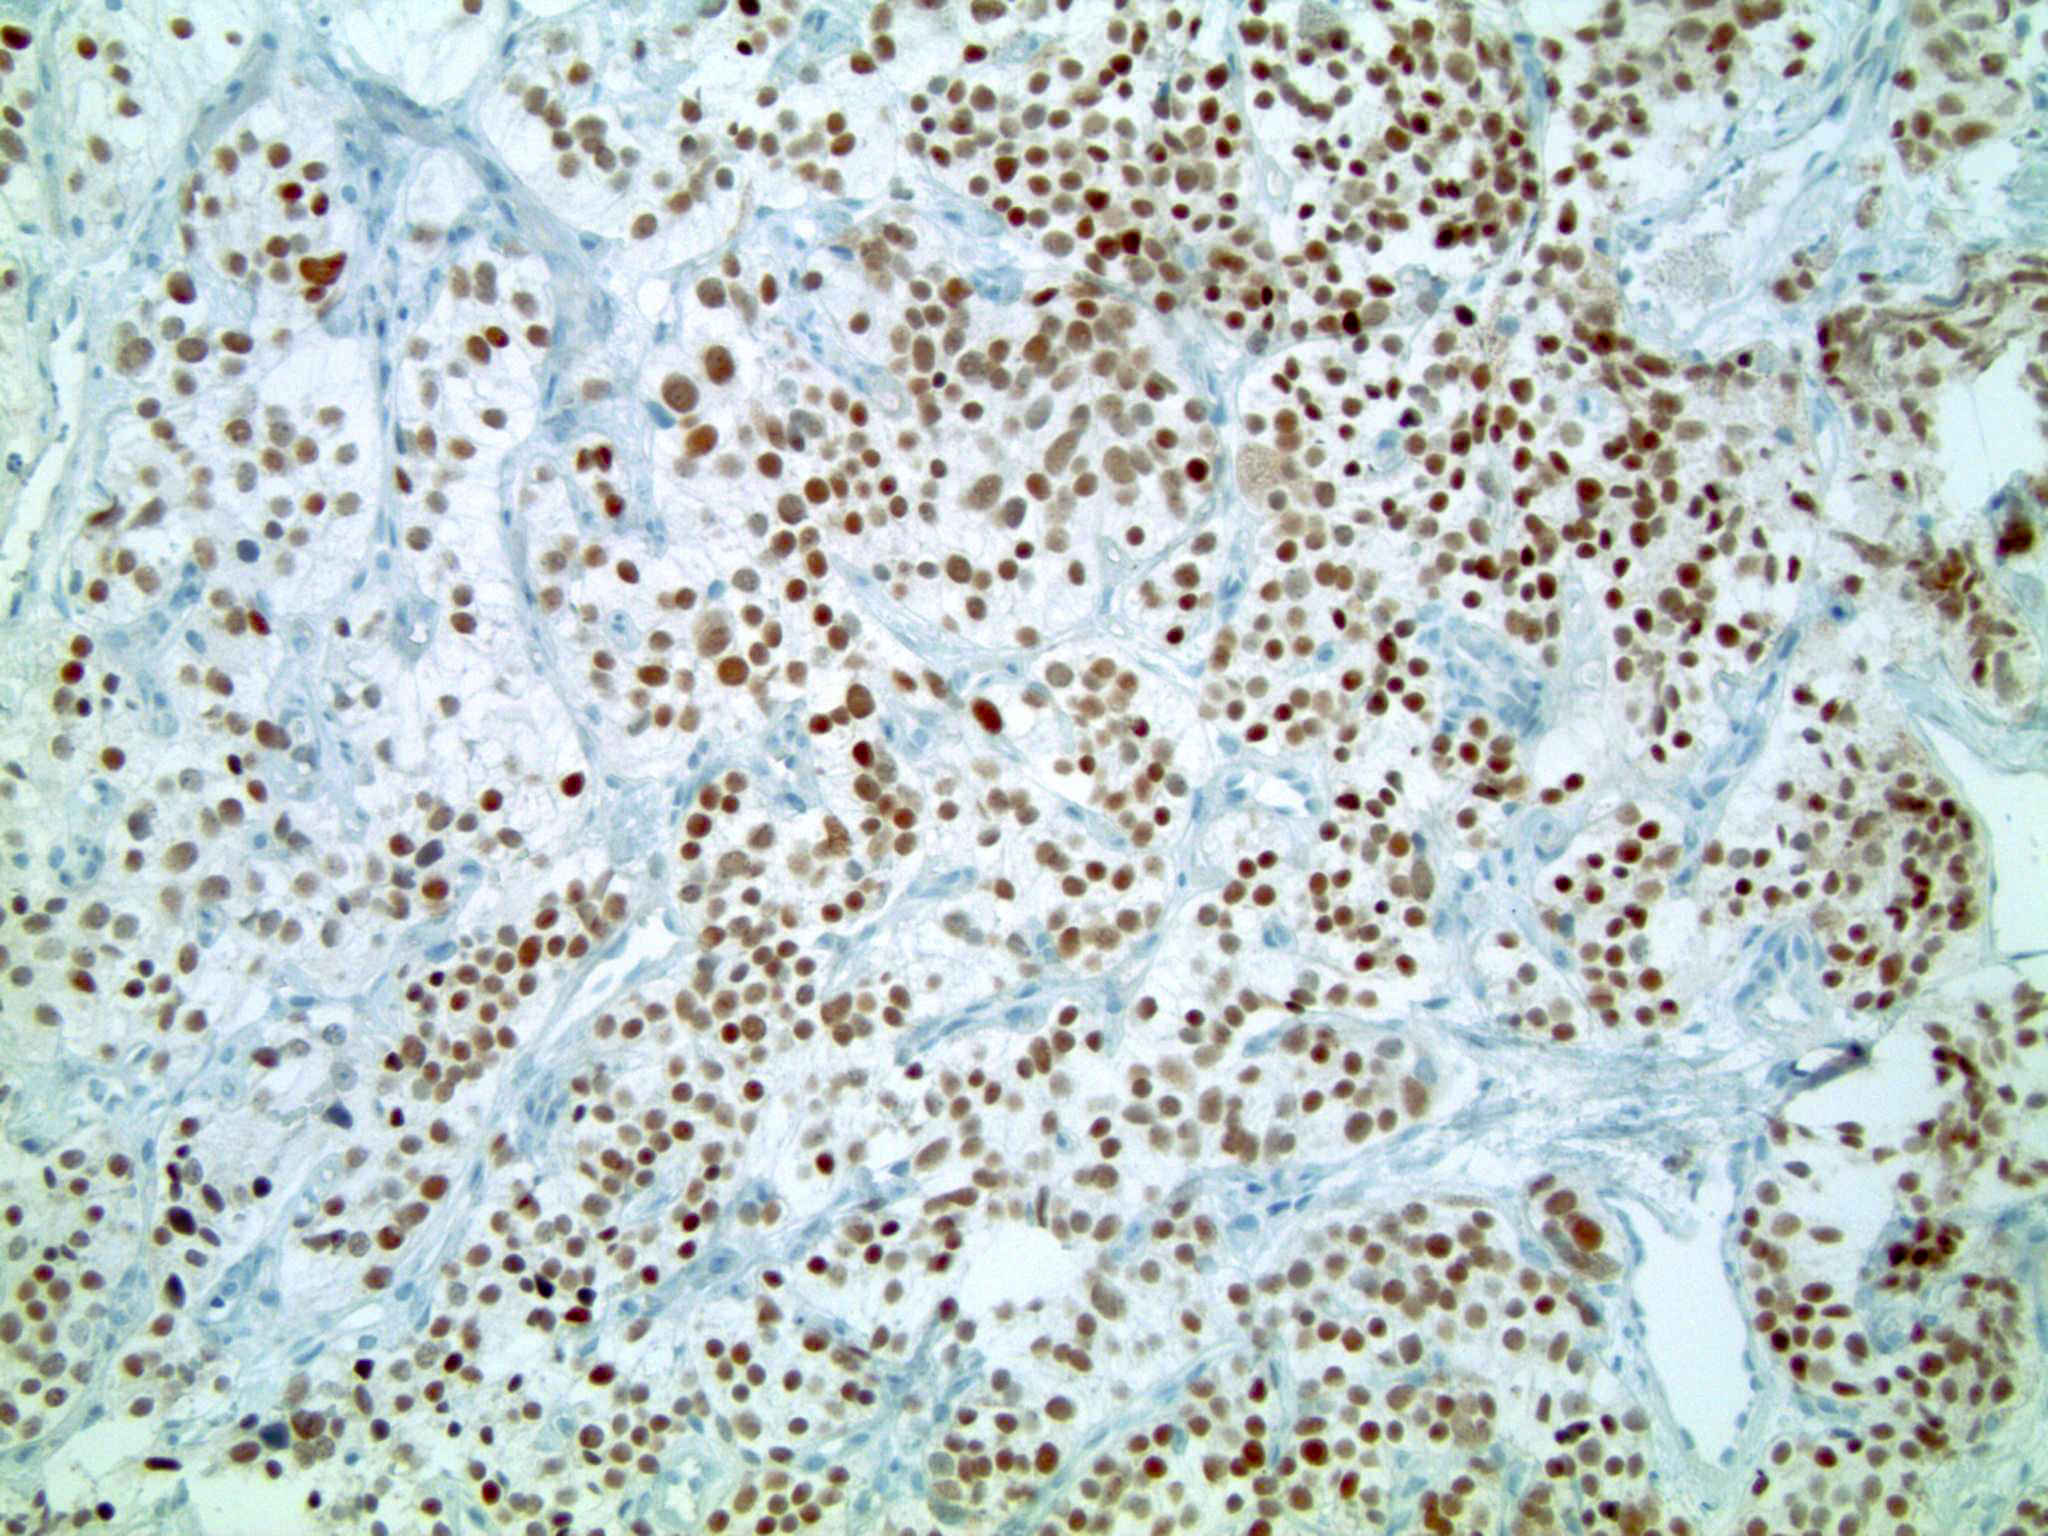

- Classic histologic morphology: monomorphic cells with abundant eosinophilic / amphophilic cytoplasm arranged in a nested / zellballen pattern and separated by fibrovascular septa with sustentacular cells

- Tumor cells are positive for GATA3 and neuroendocrine markers while negative for keratins; sustentacular cells are positive for S100 and SOX10

Microscopic (histologic) description

- Typical morphology: epithelioid cells with abundant, eosinophilic / amphophilic, granular cytoplasm and round / ovoid, vesicular / salt and pepper nuclei, arranged in a nested / zellballen pattern and separated by fibrovascular septae with sustentacular cells (Am J Surg Pathol 2004;28:94, World J Clin Cases 2014;2:591, Endocr Pathol 2022;33:90)

- May have focal pleomorphism, nuclear hyperchromasia, low mitotic activity or clear cytoplasm

Microscopic (histologic) images

Contributed by Theodorus H. van der Kwast, M.D., Ph.D., Michelle R. Downes, M.D., Debra L. Zynger, M.D. and David Cohen, M.B.B.Ch., M.D.

Positive stains

- INSM1 (diffuse), chromogranin A (variable, often diffuse), synaptophysin (variable, usually diffuse) (Endocr Pathol 2022;33:90)

- GATA3

- Sustentacular cells: S100, SOX10